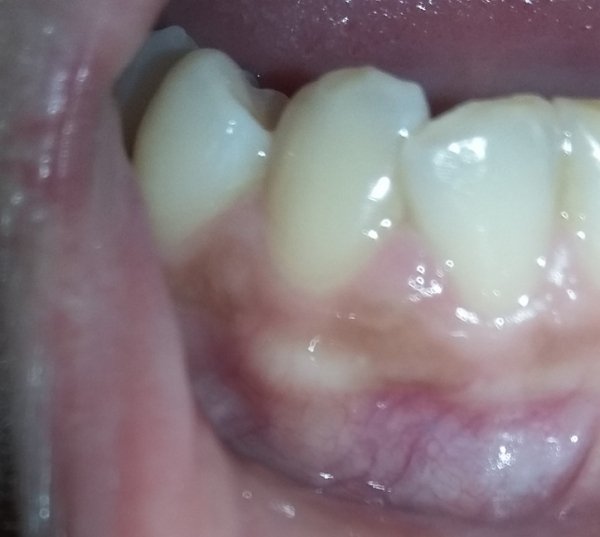

Подскажите, пожалуйста. Болела десна около недели, незначительно. Позже образовался какой-то шарик, похожий на прыщик. А после, во время еды что-то стало мешать и вот появилось непонятное новообразование из десны. На ощупь твердое, беспокоит во время приема пищи.

Подскажите, что это может быть?

Очень сложно определить, но все Ваши симптомы говорят и свищевом выходе. То есть, на верхушках зуба имеется воспалительный процесс.